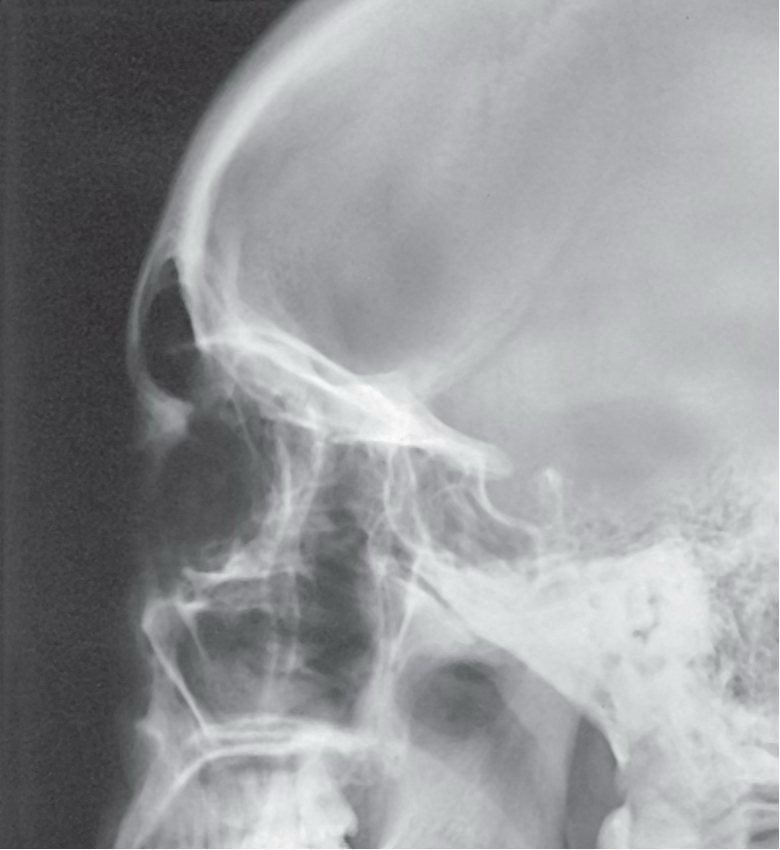

What view is this?

Lateral skull